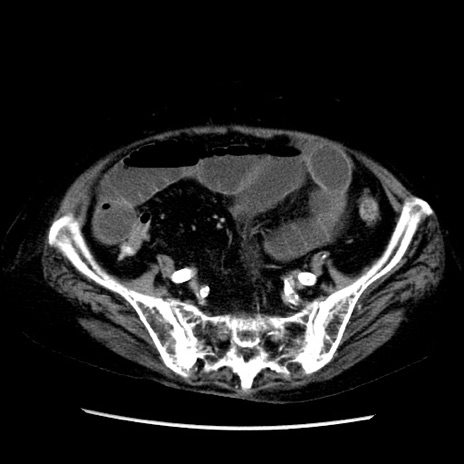

症例14(横断像)

【症例】 90歳代女性

【主訴】 腹痛・嘔吐

【現病歴】今朝から左側腹部痛を認めた。 経過観察していたが、嘔吐を認めたため来院。

【既往歴】 子宮癌術後

【身体所見】 意識清明、BP 127/54mmHg、P 98bpm Sp02 95%(RA)、BT 35.8°C、腹部平坦・軟腸ぜん動音聴取良好、右下腹部圧痛(+) 反跳痛なし

【データ】WBC 9800、CRP 0.46